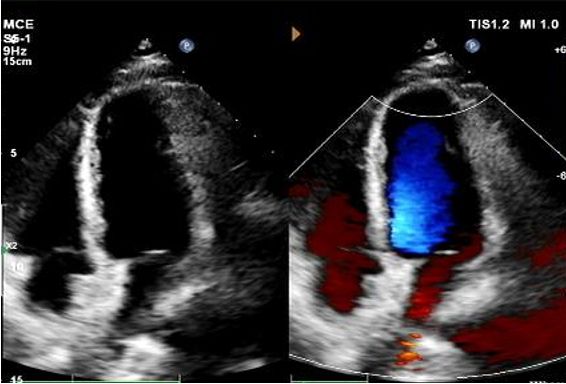

Today, we share a remarkable case highlighting 1-year post-op outcomes of MemoSorb in treating a complex long-tunnel PFO (12mm length, 1.4mm width), with a focus on serial echocardiographic evidence of device degradation and clinical symptom resolution.

Résultats clés de l'imagerie de suivi

Jour 1 à 9 mois:

Aucun shunt résiduel n'a été observé.

Réduction progressive de l'échogénicité du dispositif.

Écho d'une année:

No visible disc structures – replaced by 8mm tissue thickening at the septal implant site.

Zero residual shunt (rest or post-Valsalva).

Absorption complète de l'appareil confirmée.